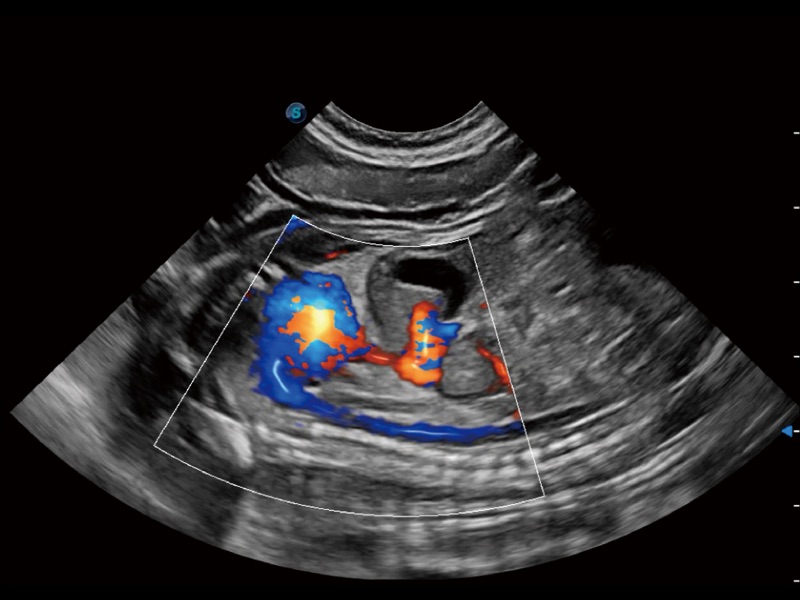

采用红、橙、黄、绿、青、蓝、紫这七种肉眼最为敏感的色彩,直观地显示组织内血流灌注的时间先后信息,更精准捕捉血流灌注走行细节。

通过创新的 Matrix E自适应滤波器和超长时间域算法,极大提升超低速微细血流的检出能力,同时更精准地滤除软组织和噪声信号,为兽用医生提供以往无法通过常规血流获得的疾病诊断信息。

通过色彩血流和实时宽景相结合,可观察到完整的静脉或动脉的血流,方便医生检查。实时扫查过程中,如有任何操作失误也可以很容易地进行回扫擦除,而不会中断扫查。